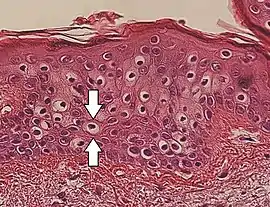

Perinuclear vacuolization of epidermal keratinocytes (one indicated by arrows), in this case an insignificant incidental finding.